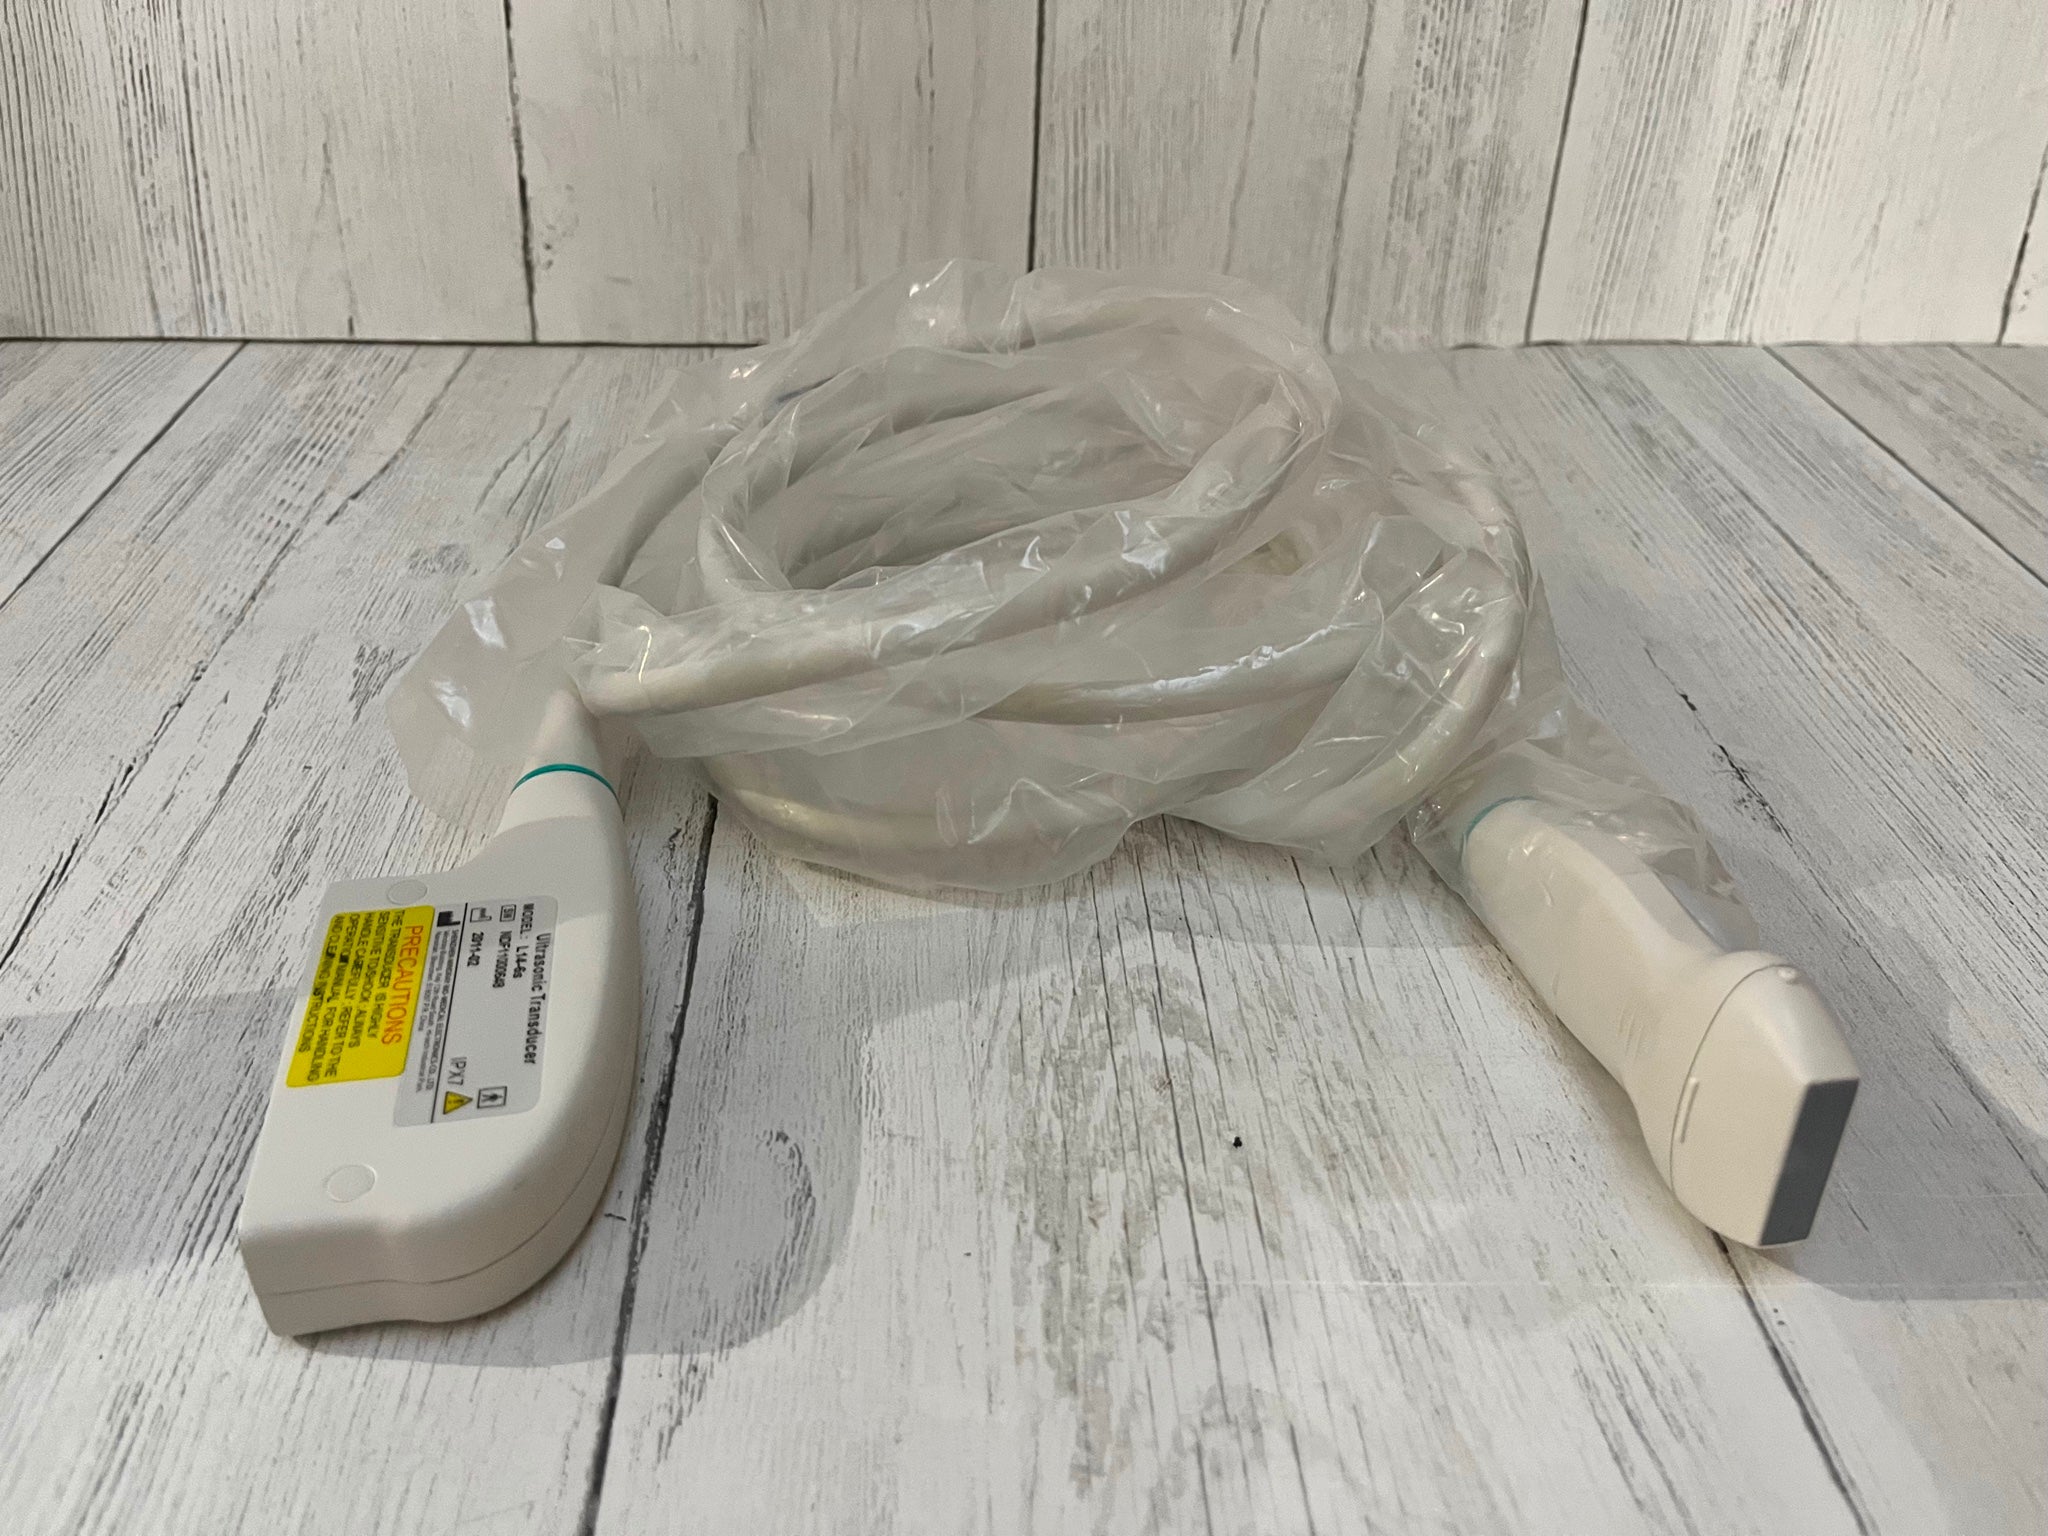

Optional: linear/transvaginal/micro-cardiac/rectal/printer